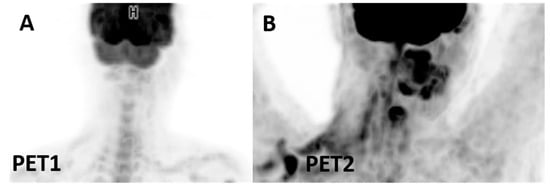

- IR(1): Progression (defined as >50% increase in overall TB) in the first 12 weeks of therapy without clinical deterioration.